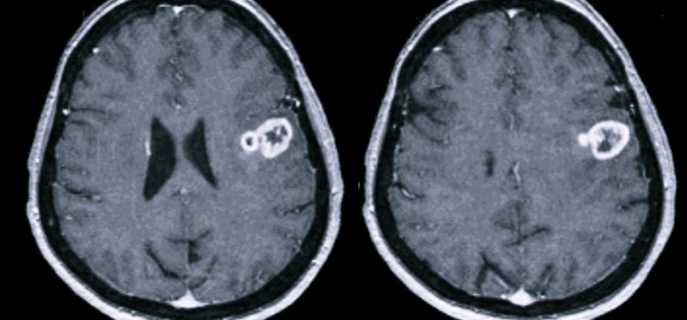

- МРТ или КТ с контрастированием – поможет определить локализацию и размеры опухоли.